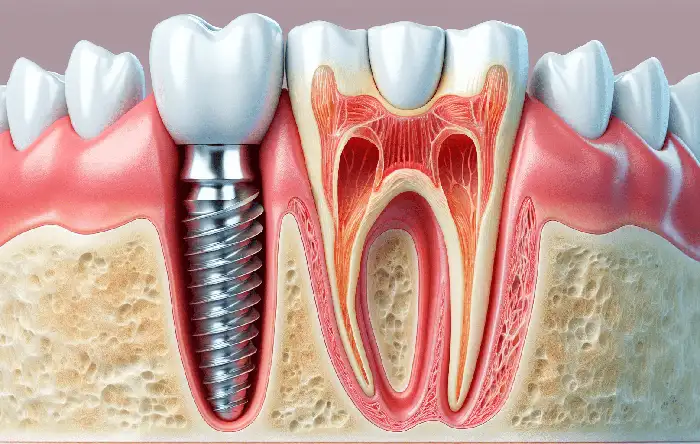

ایمپلنت دندان به عنوان یک راهکار مدرن برای جایگزینی دندانهای از دست رفته، مراحل متعددی را شامل میشود که دکتر مهدی نعمت الهی ، متخصص ایمپلنت، با دقت و حرفهایگری به انجام آنها میپردازد. در مرحله اول، ارزیابی کامل وضعیت دهان و دندان بیمار انجام میشود. این ارزیابی شامل عکسبرداری و معاینه دقیق است تا دکتر بتواند بهترین برنامه درمانی را برای هر بیمار تعیین کند. پس از آن، در صورت نیاز به درمانهای اولیه مانند پیوند استخوان، این مراحل انجام میگیرند تا شرایط لازم برای کاشت ایمپلنت فراهم شود.

در مرحله بعدی، جراحی ایمپلنت آغاز میشود که طی آن، پایه تیتانیومی ایمپلنت در استخوان فک قرار میگیرد. این عمل با دقت و تخصص بالا انجام میشود تا حداقل آسیب به بافتهای اطراف ایجاد شود. پس از نصب ایمپلنت، بیمار به مدت چند ماه تحت نظر قرار میگیرد تا فرآیند بهبود و ادغام ایمپلنت با استخوان فک به درستی انجام شود. در نهایت، زمانی که ایمپلنت به طور کامل تثبیت شد، دکتر نعمتالهی با دقت پروتز دندانی مناسب را بر روی ایمپلنت قرار میدهد تا زیبایی و کارایی دندانهای طبیعی را برای بیمار به ارمغان آورد.